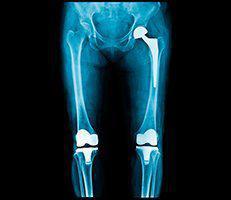

OrthoCincy Wellington Orthopaedics and Sports Medicine has provided quality orthopaedic care to patients in the greater Cincinnati area for more than 50 years. The practice has four locations in Cincinnati, a location in West Chester, Ohio, and an office in Highland Heights, Kentucky. With a large team of highly experienced physicians providing patients with specialized expertise in orthopaedic surgery, physical medicine and rehabilitation, regenerative medicine, podiatry, and sports medicine, the practice has the perfect doctor for every patient.

Each physician at OrthoCincy Wellington Orthopaedics and Sports Medicine works closely with physical therapists, hand therapists, and other clinical specialists in areas such as bracing and orthotics to create an individualized treatment plan. Thanks to their expertise in musculoskeletal treatment, research, and education, OrthoCincy Wellington Orthopaedics and Sports Medicine remains one of the largest and most respected centers in Cincinnati and the surrounding Tri-State Area.

The practice even works with Professional, collegiate, high school and developmental youth programs. From trained athletes to patients struggling with musculoskeletal conditions the specialists at OrthoCincy Wellington Orthopaedics and Sports Medicine have the experience, knowledge, and advanced treatment options to get patients back on their feet in no time. Call or book an appointment online today to learn more about the services they offer.